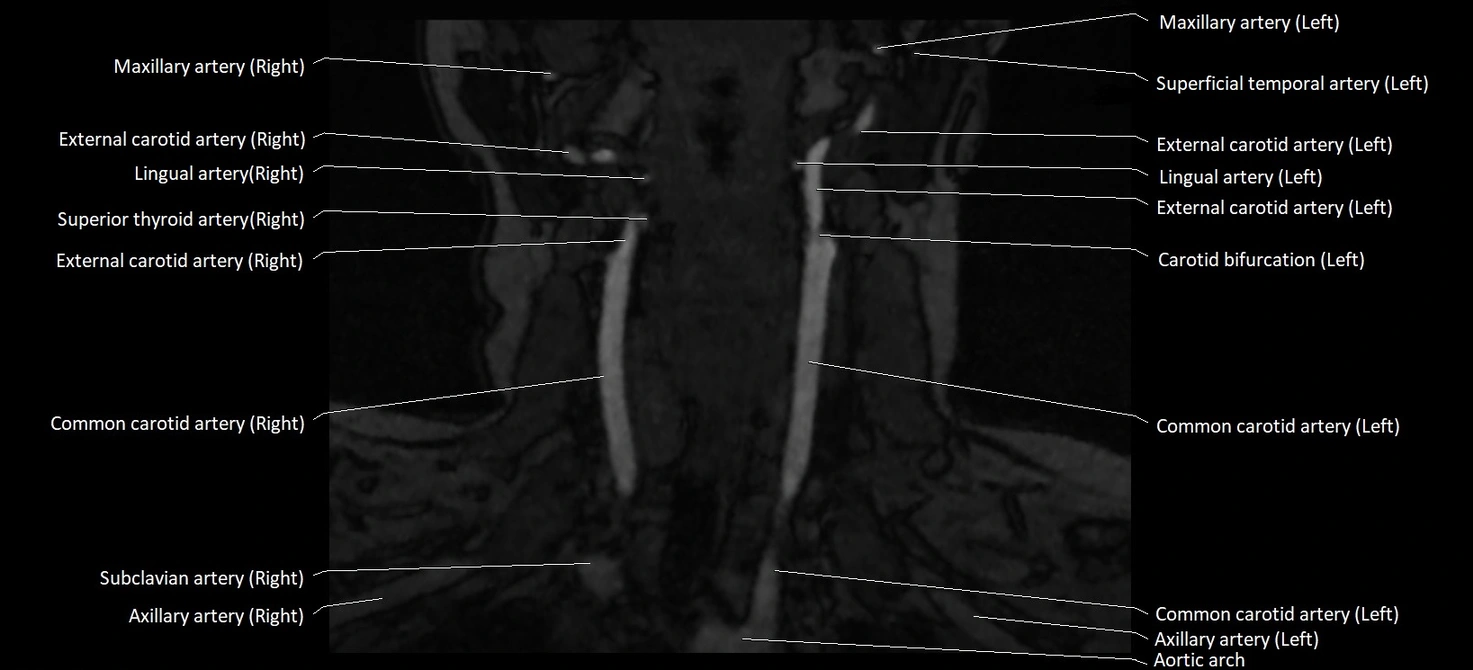

CT image

image